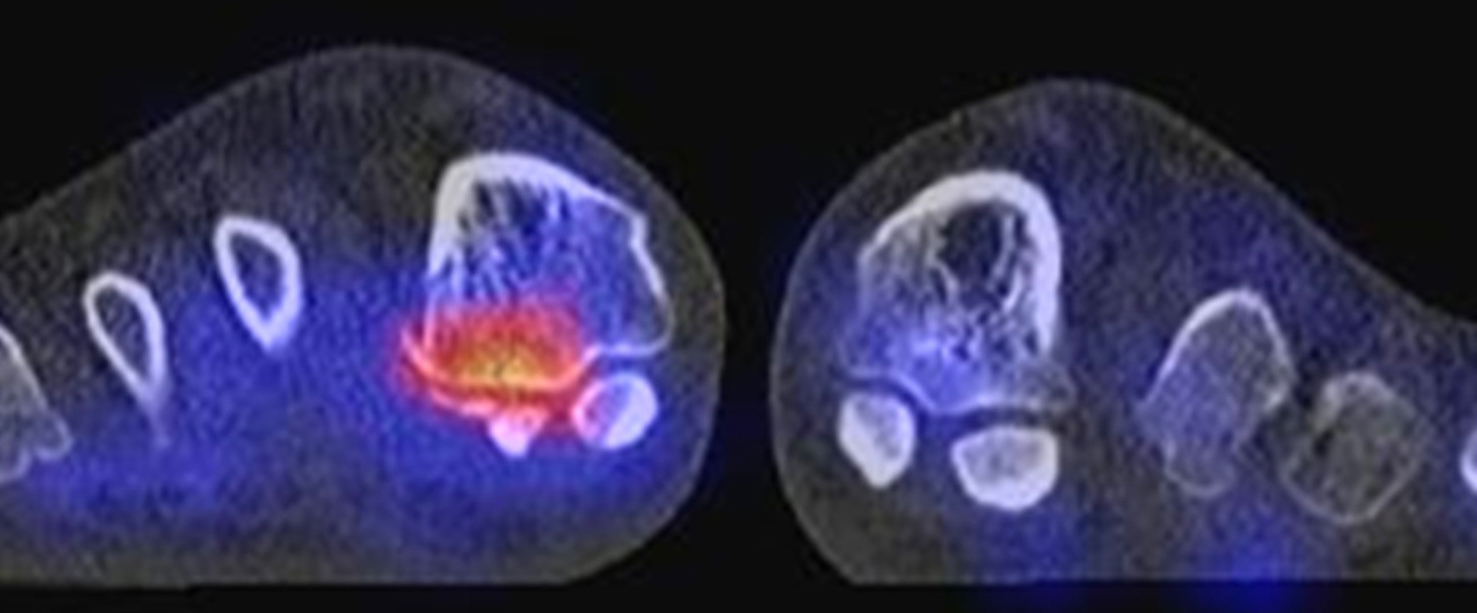

Abbildung 1.8.a und b: Akute Arthritis bei bekannter Gicht in beiden OSG: links die Früh-/Weichteilphase; rechts die Mineralisations­phase. Deutliche, entzündlich bedingte Mehranreicherungen in der Früh-/Weichteilphase. In der Mineralisation­sphase erkennt man die entzündliche Mitreaktion der subchondralen Gelenkabschnitte.

Abbildung 1.8.c - e: Akute Arthritis in beiden OSG, rechts > links. Im SPECT/CT erkennt man die Mitreaktion der subchondralen Gelenkabschnitte. Die Arthritis ist so akut, dass (noch) keine ossären morphologischen Veränderungen im CT abgrenzbar sind.